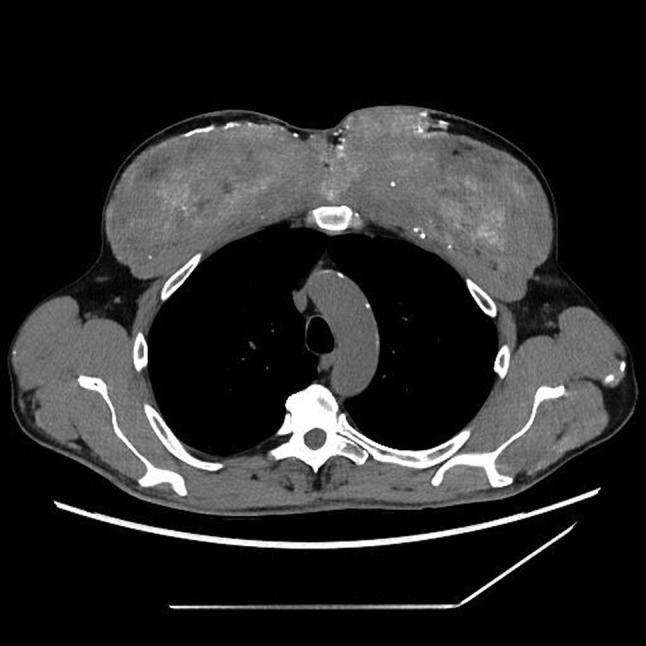

Case presentation: We report a rare trigger of increased serum calcium level - synthol intramuscular injections. A 60-year-old man who suffered from general weakness, weight loss and acute kidney injury, which were associated with unidentified hypercalcemia, was under review for proper diagnosis. We excluded endocrine disorders, malignancies, sarcoidosis, iatrogenic causes, which were defined as medication- related. Patient history, physical examination, blood chemistry, 24-hour urine collection, computed tomography and endoscopy were performed. Finally, the biopsy of muscle explained the source of the increased serum calcium concentrations.